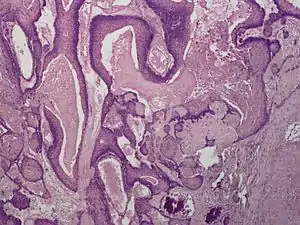

Proliferating trichilemmal cyst

Proliferating trichilemmal cysts (also known as a "Pilar tumor", "Proliferating follicular cystic neoplasm", "Proliferating pilar tumor", and "Proliferating trichilemmal tumor"[2]) are a cutaneous condition characterized by proliferations of squamous cells forming scroll-like structures.[2][3]:678

| Proliferating tricholemmal (pilar) cyst | |